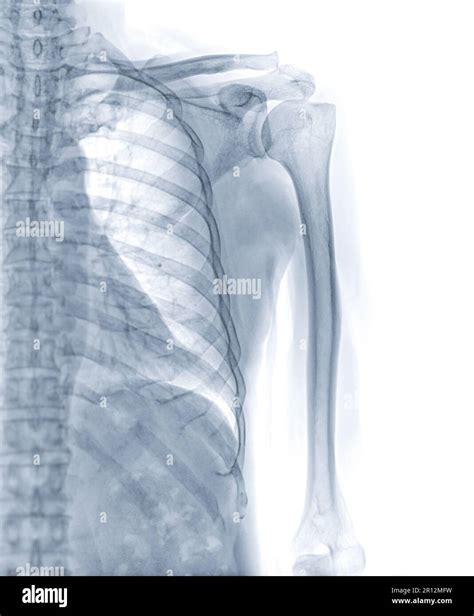

• X-rays: Imaging tests such as X-rays are used to visualize the bone and determine the type and severity of the fracture.

Proximal Humerus Fracture Occurs near the shoulder joint, often involving the head or neck of the humerus.